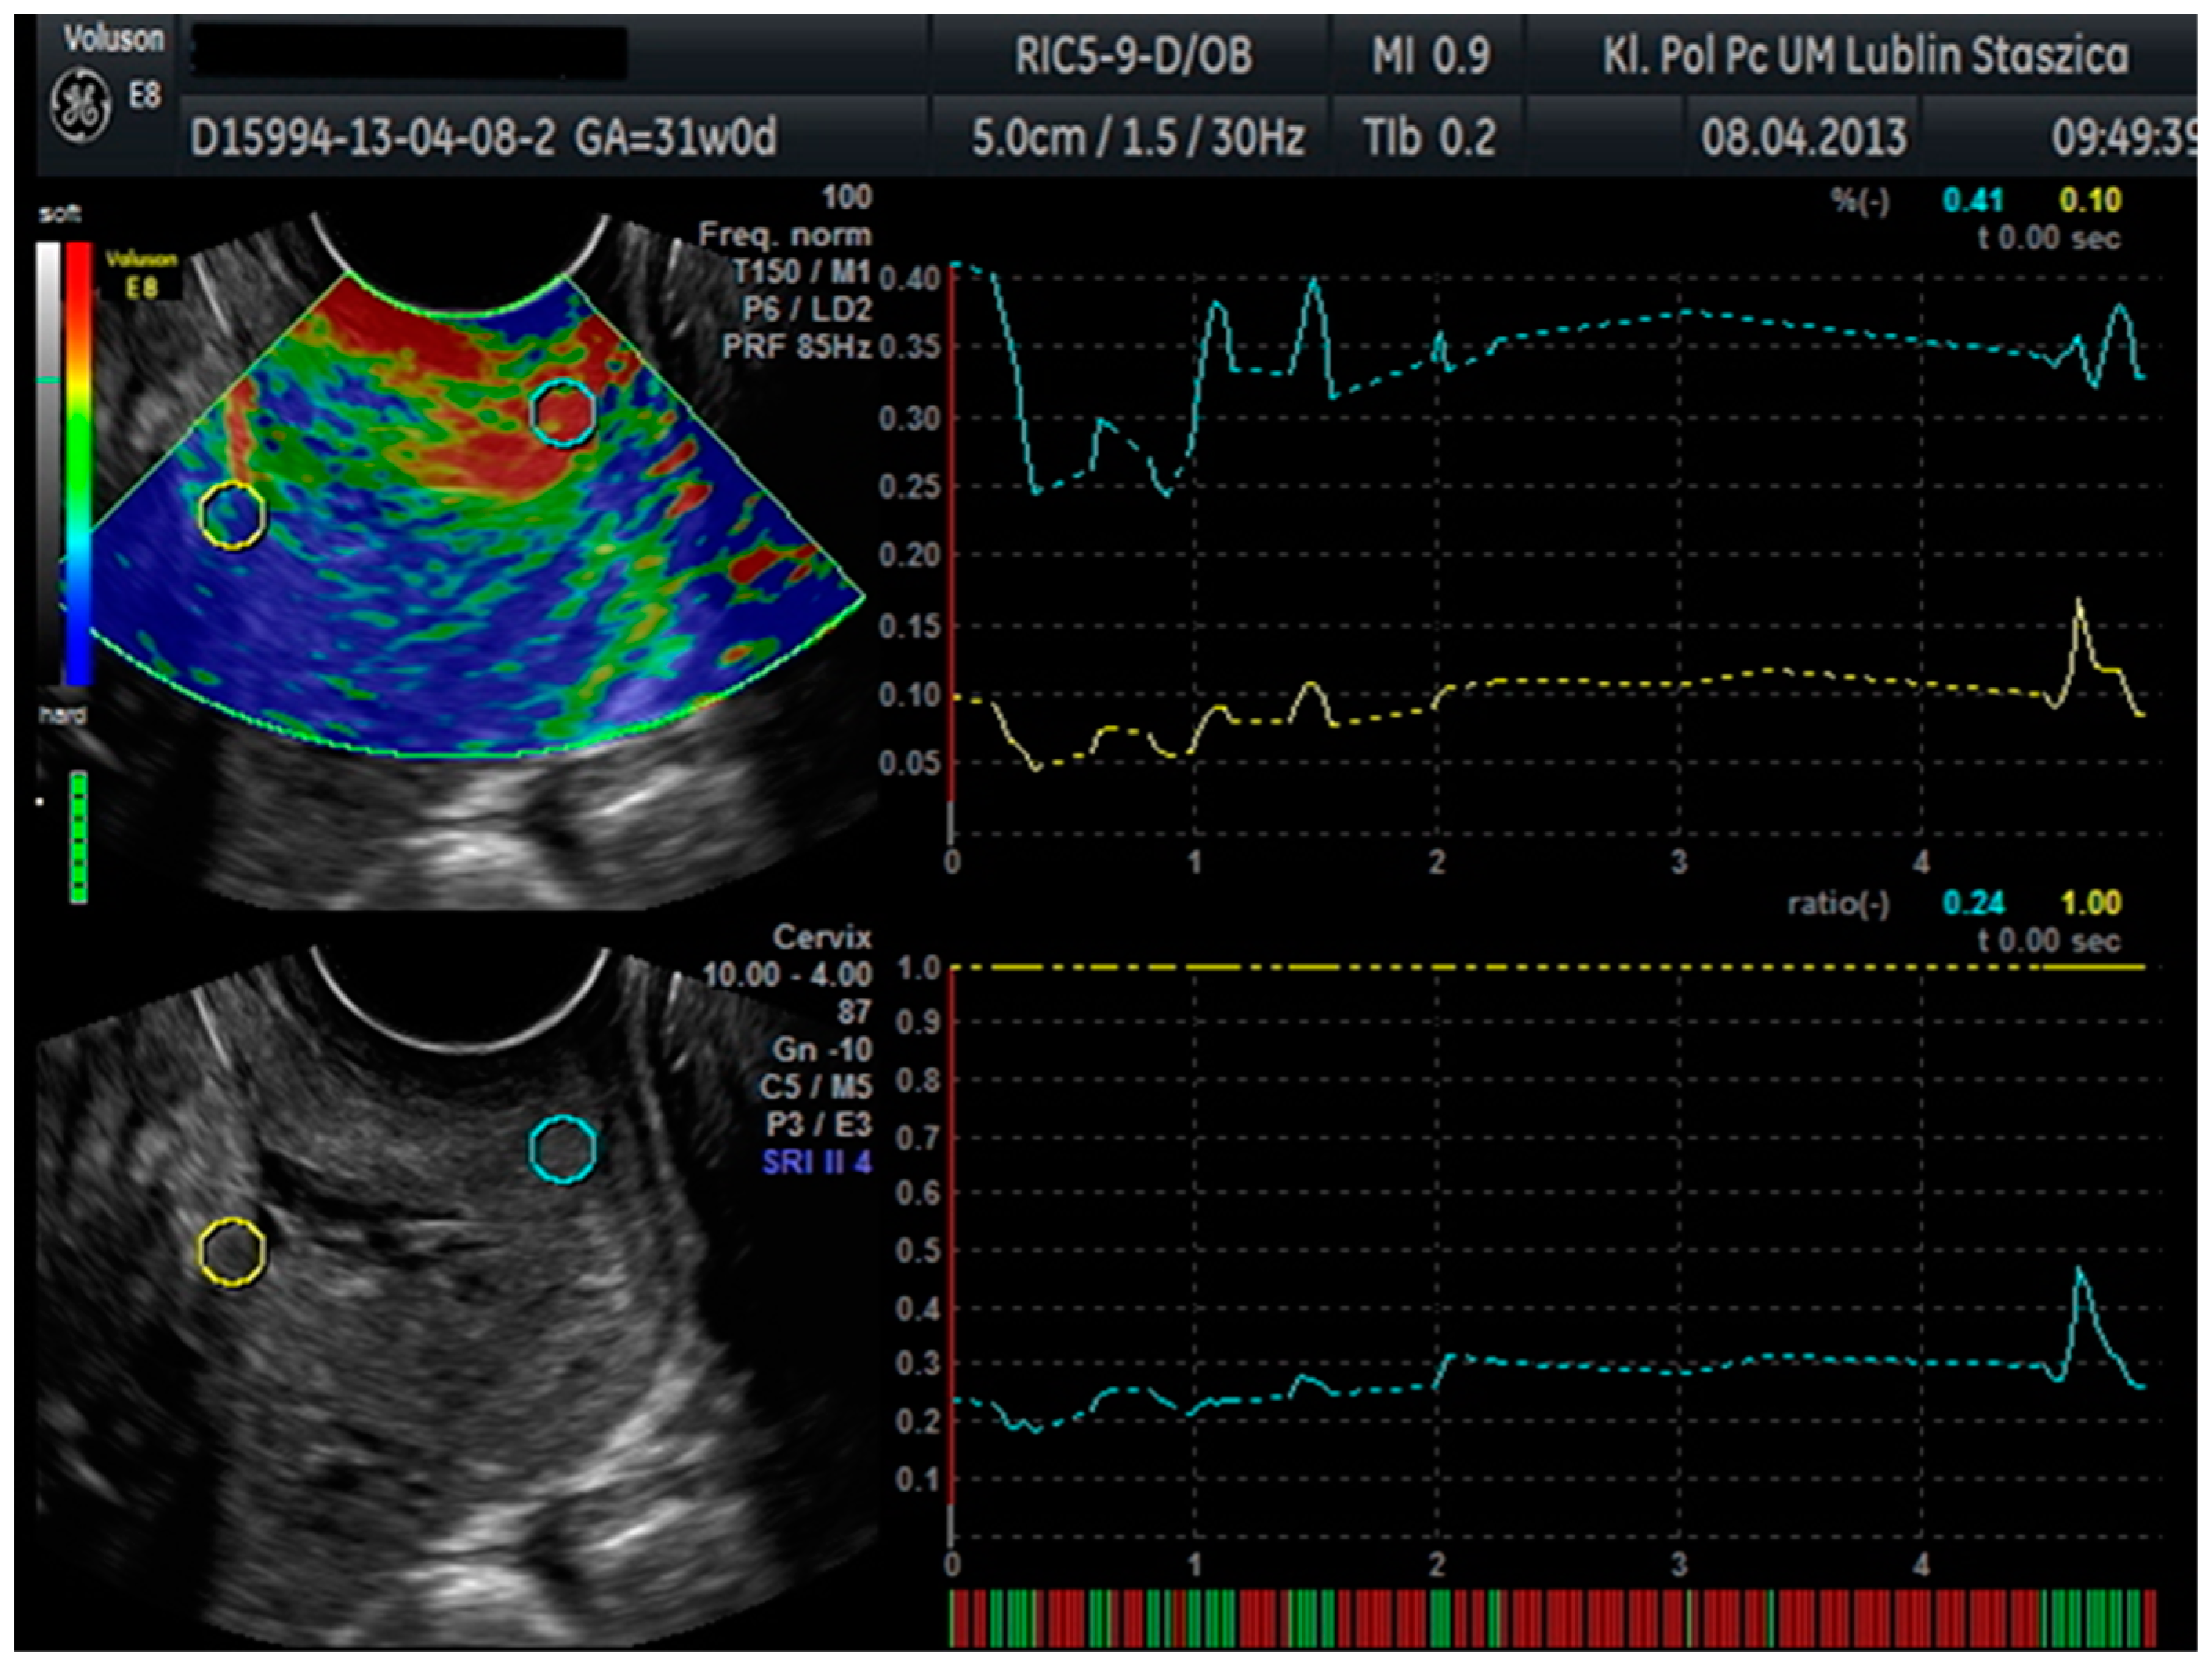

In patients hospitalized at the Department of Obstetrics and Pathology of Pregnancy at the Medical University of Lublin with symptoms of premature labor, the diagnostic standard is an ultrasound examination, in which, in addition to the assessment of the fetal biometry and anatomy, the length of the cervix was determined. Blood samples were also collected from the patients included in the study, and a swab was taken from the posterior vaginal fornix during the gynecological examination preceding the ultrasound examination. The VolusonTM E8 with Elastography Analysis mode was used for the ultrasound examination. An endovaginal ultrasound was performed using an endoscopic probe (VolusonTM E8, RIC5-9-D). During the examination, the patients were asked to assume the lithotomy position. An endovaginal probe was placed in the anterior vaginal fornix, and the bladder was identified as an orientation point. A standard sagittal image of the cervix was then obtained, and the length of the cervix was measured. The probe, with elastography mode on, was used to produce up to five compression and decompression cycles. After confirming the correct compression and manual decompression in the form of a green quality bar in the lower-left corner of the screen, a measurement was made with each cycle lasting about 1 s. During each cycle, a tissue shift of approximately 1 cm was achieved. On the images obtained in this way, two regions were selected: area A on the upper cervical lip and area B on the bones of the fetal skull as the hardest reference point. Within these areas, circles of 5 mm in diameter were placed. From these circles, the Elastography Analysis program computed numerical values for the strain ratio and SR (SR–comparative tissue measurement). The value of the deformation factor means compression. The maximum value of compression in human tissue is 2%. The SR value, or comparative tissue measurement, indicates how much the tissue in the test area is harder or softer than the tissue in the reference test area. From these values, the means were calculated and used for statistical calculations (Figure 1).

Figure 1. Cervical elastographic evaluation in the Elastography Analysis program.